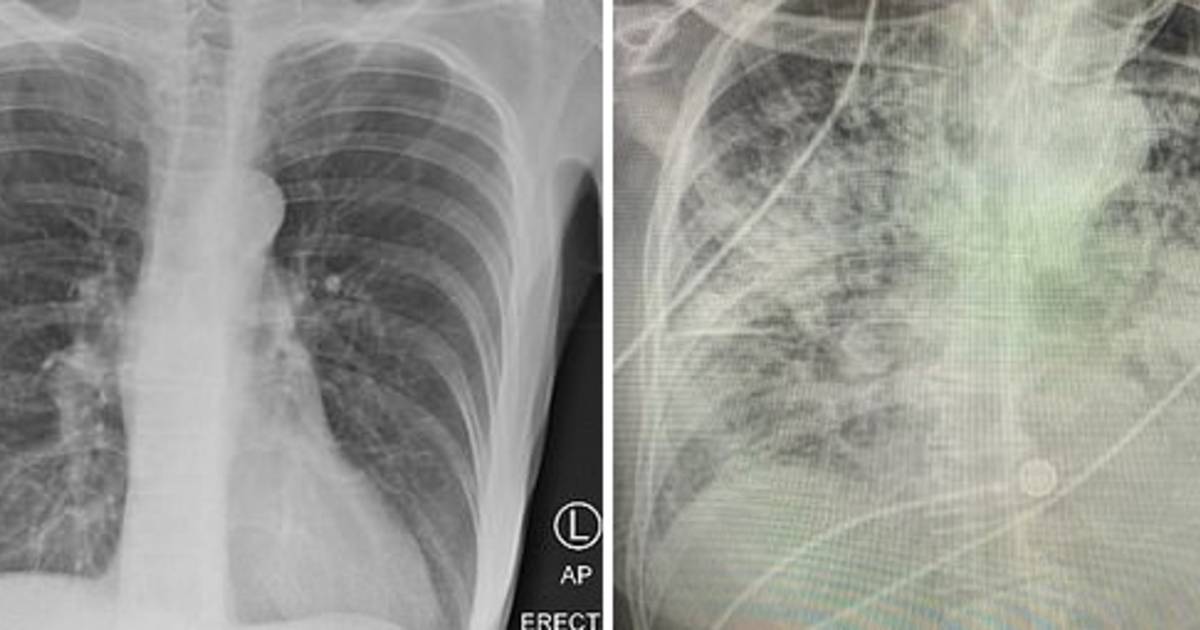

Op röntgenfoto's of scans kunnen deze gezwellen eruitzien als een schaduw of vlek op de long Als uw arts een longknobbeltje op een röntgenfoto van de borstkas of CT-scan ziet, raak dan niet in paniek.

Source: mailbackent.pages.dev Witte Vlekken Op Nagels Alimta® 🏥 ziekte, symptomen, behandeling. 2021 maitildezivie , Op longfoto's ziet deze ernstige vorm eruit als een patroon van streepjes en vlekjes, meestal in het midden van de longen. De meeste longknobbeltjes zijn geen teken van longkanker en hebben geen behandeling nodig

Source: juntallamg.pages.dev CONFETTIHUID, witte vlekjes op benen en armen Schoonheidssalon "PUUR Huidinstituut" Oosterhout , Op longfoto's ziet deze ernstige vorm eruit als een patroon van streepjes en vlekjes, meestal in het midden van de longen. Een vlek op de long, zonder duidelijke oorzaak, moet dus onderzocht worden, rekening houdend met de risicofactoren van de patiënt, zoals leeftijd en rookgewoonten.

Source: ravpacnbx.pages.dev Witte Vlekken Op Röntgenfoto Longen Wat Betekent Dit? , Intrapulmonale tumoren geven ook witachtige schaduwen op de röntgenfoto van de borstkas.Longkanker is in verschillende landen een van de belangrijkste oorzaken van oncologische sterfte. Op röntgenfoto's of scans kunnen deze gezwellen eruitzien als een schaduw of vlek op de long

Source: ruheathray.pages.dev Wat als je niet meer beter wordt? Uitzaaiingen in botten, longen, lever, hersenen 2/6 YouTube , In de longen kunnen blastomen zich manifesteren als knobbeltjes Röntgenfoto's van de borst of tomografie zijn de tests die gewoonlijk worden gebruikt om de toestand van de longen te zien, deze worden uitgevoerd.